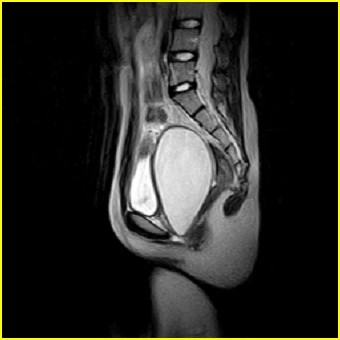

女、15岁、下腹疼痛2天,排尿困难1天。查体:处女膜闭锁,距处女膜约4至5cm处扪及一约5cm直径的圆形包块,张力较高,触痛明显、欠活动。b超提示子宫增大伴宫内增强回声团。

影像意见:子宫直肠陷凹积血。

更正影像意见:阴道积血。

处女膜闭锁,阴道积血,子宫积血.

阴道积血,子宫积血.

子宫及阴道积血。

处女膜闭锁,伴子宫及阴道积血.